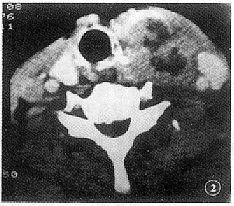

21例腺瘤增强后9例显示瘤周完整强化环,5例瘤内强化结节(图1),3例瘤灶轻微强化,4例低密度囊性灶无强化;8例腺癌增强后2例显示瘤壁乳头状强化结节,6例癌灶不均匀强化(图2)。

图2 甲状腺癌:增强CT扫描示甲状腺左叶不规则形混杂密度肿块,边不清,强化不均,病理证实为甲状腺髓样癌